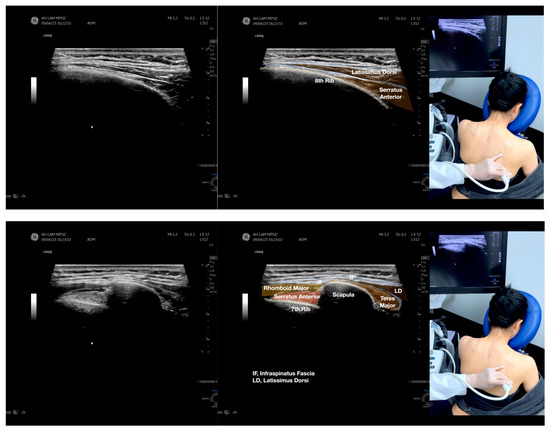

Figure 2.

Sonoanatomy of the lateral border of the inferior trapezius, its related muscles, and the infraspinatus fascia. The step-by-step scanning techniques of the structures illustrated in this figure have been shown in Video S6. Available online: https://www.dropbox.com/s/vjj49wiwdsidouz/Figure%202.docx?dl=0 (accessed on 1 January 2023). Dynamic ultrasound scanning of the anterior shoulder with the humerus externally rotated (palm up), elbow straight, and the shoulder actively flexed and abducted at about 90 to 100 degrees shows that the fibrotic and thickened bursa was noted to be snapping between the subscapularis tendon and the coracoacromial ligament, as shown in Video S3. The patient noticed this snapping during many of his daily activities with his shoulder flexed just above 90 degrees, e.g., taking off clothes and combing hair. Ultrasound-guided injection of the thickened and fibrotic bursa did not reproduce the usual pain nor reduce the pain, and it did not improve the shoulder snapping and flexion power with the elbow straight, shoulder flexed to 90°, and the humerus externally rotated (palm up). Ultrasound-guided injection of the cortical break reproduced the concordant pain and temporarily and partially reduced the pain with snapping and residual anterior shoulder pain (Video S4), but it did not change the snapping or weakness in the right shoulder flexion with the humerus in external rotation. With the failure of direct anterior treatment to the suspected lesions, it was essential to further explore other causes for the anterior painful snapping. Further detailed musculoskeletal examination of the scapular movement showed that the right scapulothoracic movements were not smooth compared to the left counterpart (Video S5) [4,5]. There might be some disruptions in the right infraspinatus fascia (IF) and its related muscles, including the lateral edge of the right inferior trapezius, rhomboid minor and major [6], teres major, latissimus dorsi [7,8] (LD), and posterior deltoid attachments to the IF [9,10]. Clinically, prominent and active trigger points were observed in the right infraspinatus muscle. Holding the inferior angle of the scapula, with the examiner’s fingers, especially over the origin of the teres major muscle over the scapula, the latissimus dorsi [11,12,13] and the scapular insertion of the rhomboid major muscle significantly improved the power of the resisted shoulder flexion with the elbow straight and the shoulder flexed to 90° with the humerus externally rotated (palm up). In order to illustrate the utilization of ultrasound-guided sonopalpation and ultrasound-guided digital palpation for detecting the suspected lesions of the IF and its related muscles, we presented the following videos (Videos S6–S9) and still images (Figure 2, Figure 3, Figure 4 and Figure 5) to demonstrate the essential techniques and crucial points of getting the normal sonoanatomy of the IF and its related structures. The gross anatomy of the IF and its related muscles were also shown in Figure 6, Figure 7 and Figure 8.